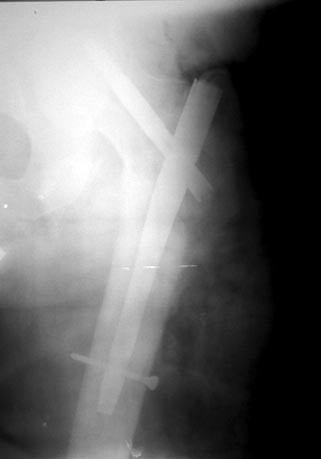

Сегодня сделали операцию. Снимки интраоперационные, аксиальный не

"публикую" еле видно. Поверьте на слово - стержень прошел через центр

шейки, в обоих плоскостях. Других вариантов не было из-за следов

предшествующего вмешательства. Хотели-бы обсудить результат в свете

послеоперационного ведения (какую разрешать активность, в какие сроки).